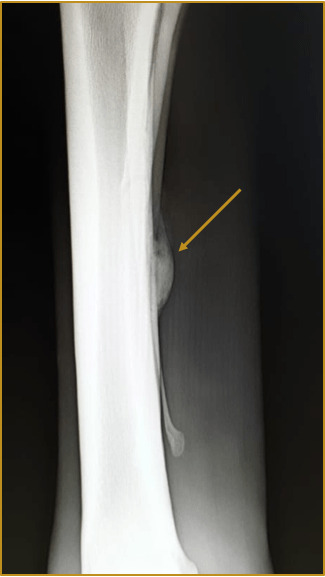

Pferde mit Überbeinen zeigen knöcherne Zubildungen an den Röhrknochen der Beine. Sie können einseitig, aber auch an mehreren Gliedmaßen auftreten. Je nach Lokalisation werden sie in seitliche, hintere und tiefe Überbeine eingeteilt.

Weitere knöcherne Zubildungen können aufgrund eines Griffelbeinbruchs entstehen oder der Schienbeinkrankheit. Letzteres tritt häufig bei jungen Vollblütern im Rennsport auf. Durch das intensive Galopptraining wird das noch nicht fertige Skelettsystem stark belastet, dies versucht sich dieser Belastung anzupassen und so steht die Bildung dieser Zubildung im direkten Zusammenhang mit dem Training.

- Röntgen